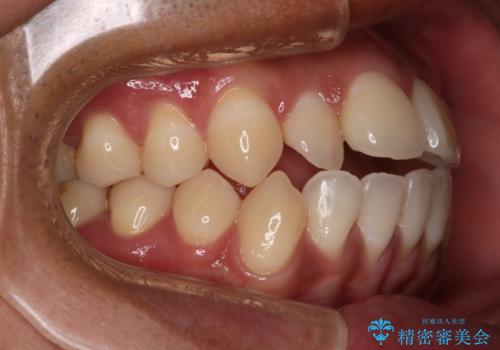

開口(オープンバイト)のため噛み合わせを考慮してワイヤー矯正を提案させていただきました。

IPR(歯と歯の間を削る処置)と顎間ゴムを行い歯並びを整える治療計画を立てました。